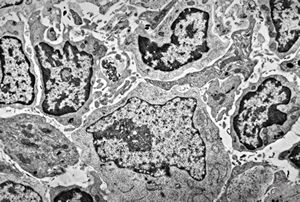

F,52y. | bone marrow - inclusions in plasmocytes

M,62y. | bone marrow - plasmocytoma - inclusions